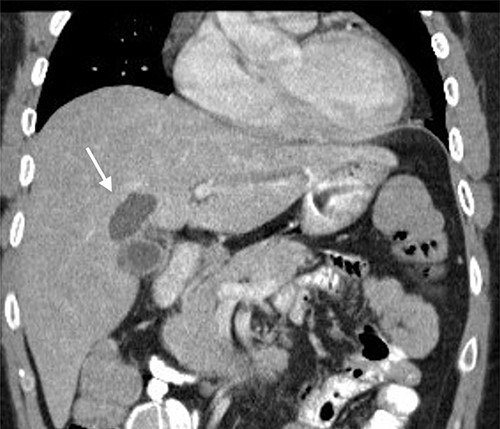

A 35-year-old man presented with a history of recurrent episodes of epigastric pain. Ultrasonography revealed an intrahepatic cyst (Fig. 1), and magnetic resonance cholangiography revealed that the cyst was connected to the cystic duct and right anterior sectoral bile duct (Fig. 2). The patient underwent an endoscopic retrograde cholangiography, which showed that the contrast could fill the cyst (Fig. 3). The laboratory findings, including a complete blood count, showed a white blood cell count of 4200/mm3 (lymphocyte 23%, neutrophil 62%); haemoglobin level of 16 g/dL; platelet count of 215 × 103/ mm3; total protein of 7.8 g/dL; albumin of 4.3 g/dL; total bilirubin level of 0.68 mg/dL; serum aspartate aminotransferase level of 26 IU/L; serum alanine aminotransferase level of 29 IU/L and alkaline phosphatase level of 105 IU/L. Tumour markers, including alpha-fetoprotein, carcinoembryonic antigen and carbohydrate antigen 19–9 were within normal limits. Viral markers for hepatitis B and C were negative. Due to the preoperative diagnosis of a type VI choledochal cyst, with a differential diagnosis of cystic intraductal papillary neoplasm of the bile duct, the patient underwent laparoscopic right anterior sectorectomy to excise the cyst completely. During the operation, after identifying the cystic duct and taking down the fundus and body of the gallbladder from the liver bed, an intraoperative cholangiogram was performed via the cystic duct connected to the cyst. Right anterior sectorectomy was then performed (Fig. 4). The postoperative period was unremarkable, and the patient was discharged on the sixth postoperative day. Pathological examination revealed a cyst with a fibrous wall, dense chronic inflammatory infiltration, lined by columnar epithelium. Mild reactive atypia, associated with marked chronic inflammatory cell infiltration, was noted. No signs of epithelial dysplasia were observed (Fig. 5).

Computed tomography image showing an intrahepatic cyst (arrow).